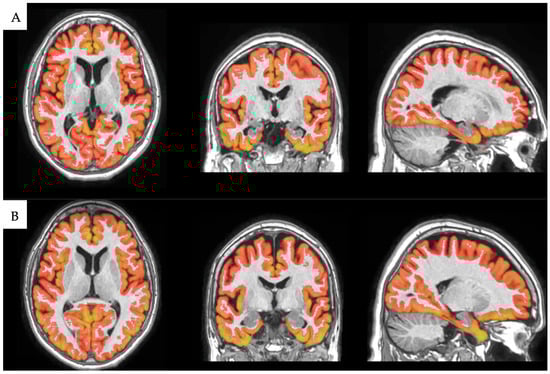

2.3. Image Processing

Volumetric Analysis with volBrain